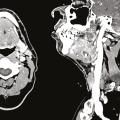

Pathologies lithiasiques des glandes salivaires

Parmi les pathologies des glandes salivaires, les lithiases des canaux salivaires sont les plus fréquentes, avec une incidence entre 1 pour 10 000 et 1 pour 20 000.1 Elles représentent environ 60 % des cas d’obstruction des canaux salivaires et s’observent à tout âge. Les lithiases sont plus fréquemment retrouvées dans les…